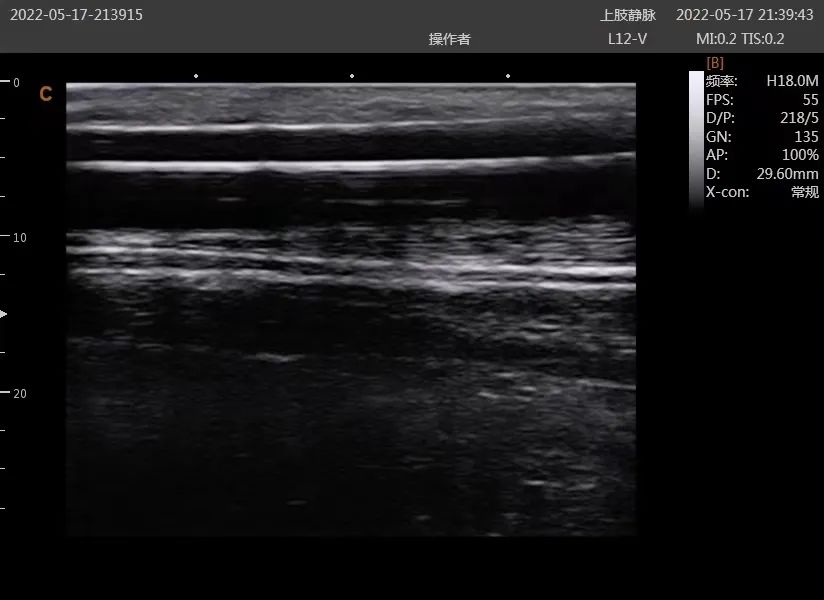

病例2:术前B超提示动静脉内瘘流出道静脉狭窄,血管内径1.8mm